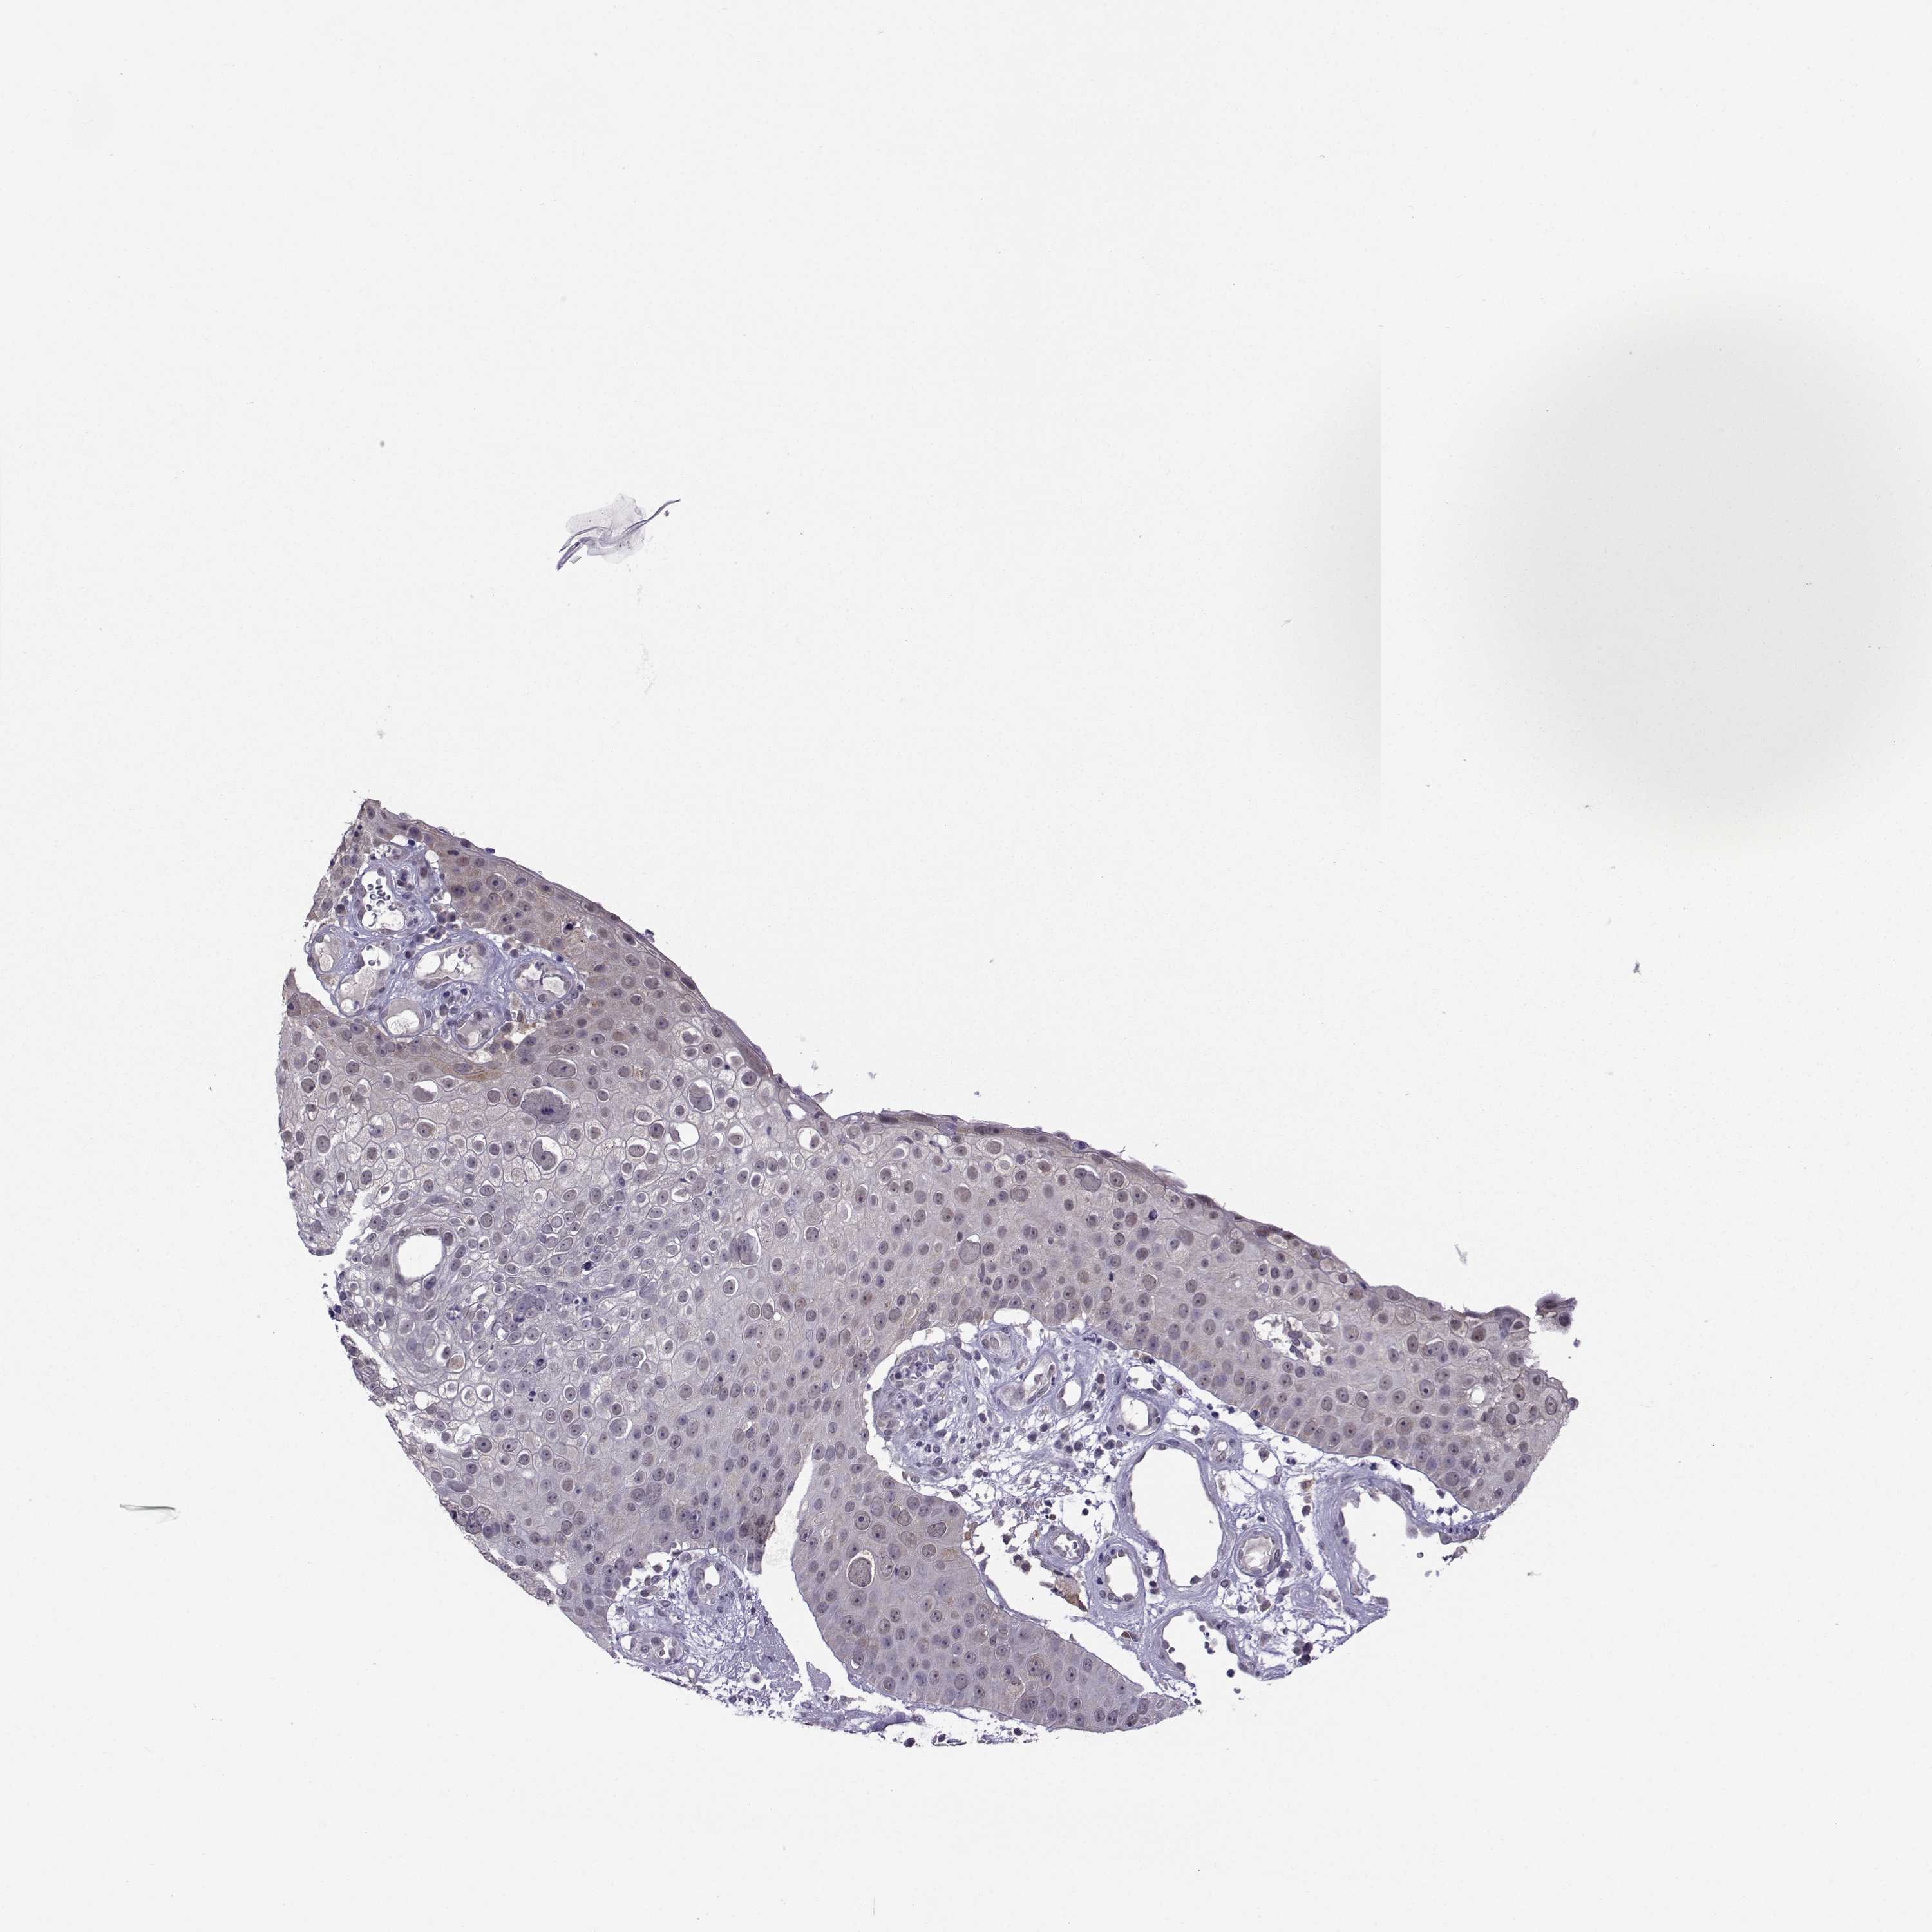

Basal cell and squamous cell cancer

SKIN CANCER - Protein expressioni

A mouse-over function shows sample information and annotation data. Click on an image to view it in a full screen mode. Samples can be filtered based on level of antibody staining by selecting one or several of the following categories: high, medium, low and not detected. The assay and annotation is described here.

Antibody stainingi

Antibody staining in the annotated cell types in the current human tissue is reported as not detected, low, medium, or high, based on conventional immunohistochemistry profiling in selected tissues. This score is based on the combination of the staining intensity and fraction of stained cells.

Each image is clickable and will lead to virtual microscopy that enables deeper exploration of all samples and also displays staining intensity scores, fraction scores and subcellular localization as well as patient and tissue information for each sample.

Antibody HPA005516

Antibody CAB015427

Basal cell carcinoma

Squamous cell carcinoma, NOS